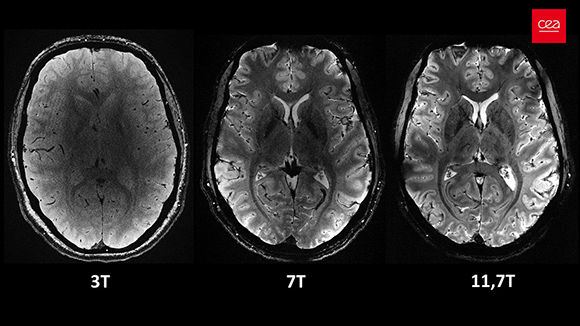

מסוגל לסרוק בכושר הפרדה (רזולוציה) של 0.2 מ”מ ולסיים את סריקת כל החתכים במוח בתוך ארבע דקות בלבד. מוח ב-MRI בעוצמה של 11.7 טסלה (מימין) לעומת מכשירים חלשים יותר | © CEA

הכלים המשמשים אותנו בחקר המוח החי ממשיכים להשתכלל, ובין השאר נעשה שימוש במכשירי MRI יותר ויותר חזקים שמספקים סריקה אנטומית מפורטת במיוחד. המכשיר החזק ביותר כיום נמצא בצרפת ועוצמתו מגיעה ל-11.7 טסלה. הוא מסוגל לסרוק בכושר הפרדה (רזולוציה) של 0.2 מ”מ ולסיים את סריקת כל החתכים במוח בתוך ארבע דקות בלבד. לשם ההשוואה, במרבית בתי החולים בישראל נעשה שימוש במכשירי MRI בעוצמה של 1.5 טסלה, שמספיקים לרוב הצרכים הרפואיים. למחקרי מוח נהוג להשתמש במכשיר בעוצמה של 3 טסלה, ובמכון ויצמן למדע קיים מכשיר אחד שמגיע ל-7 טסלה.

לעוצמה הגבוהה של השדה המגנטי יש מחיר – הנבדקים עלול לסבול מבחילות וסחרחורות, דבר שמגביל את משך הניסויים שאפשר לעשות בו. בנוסף, תחזוקתו של המכשיר מורכבת ויקרה מכיוון שהסלילים המפיקים את השדה המגנטי צריכים להיות מקוררים לטמפרטורה הקרובה לאפס המוחלט. הקירור דרוש על מנת שתהיה פחות התנגדות, ויתאפשר מעבר הזרם החשמלי היוצר את השדה המגנטי. כך שלמרות יתרונותיו, מכשיר חזק במיוחד אינו בהכרח הבחירה האופטימלית לניסוי, ויש לקחת בחשבון שיקול נוספים.